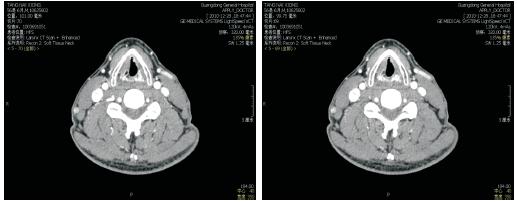

2012-05-18喉部增强CT:喉癌术后, 左侧舌骨术后改变, 与2010-12-28 CT对照, 原左侧声带小结节消失, 新增左侧声带中部小结节, 见图2和图3。诊断:左侧声门型鳞状细胞癌术后局部复发rT2N0M0 Ⅱ 期, 无病生存期17个月, 建议进一步检查。

考虑到患者是喉癌术后复发, 建议患者行全喉切除术, 但患者拒绝全喉切除术和半喉切除术, 只接受激光切除术。2012-05-25行支撑喉镜下喉肿物切除术, 术后病理为:(喉恶性肿瘤)鳞状细胞癌, 高分化。